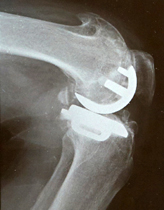

半置換術用のインプラント例と術後のX線

軟骨がなくなって強い痛みがあり、自由に歩けない状態―これが一般的な人工膝関節置換術の適応基準です。人工関節に置き換えると、膝の痛みを劇的に取り除くことができますので、残りの人生を痛みなく動けるようにする・最期まで自分の脚で動けるようにするというのが、人工膝関節置換術の目的になります。入院する時には車イスだった人でも、自分の脚で杖をついて歩けるようになって帰ることができます。痛いけれど我慢して制限のある生活をするか、残りの人生をできれば痛みなく自由に動ける生活をしたいか、各人の望みは決して同じではありません。「縁側で座って猫を抱いているのが幸せ」という人には、無理に人工関節は勧めません。患者さんの目的に合わせた、別の治療法を選択すればいいと思っています。人工膝関節置換術には、関節を全て置き換える「全置換術」と軟骨のすり減った片側だけを置き換える「半置換術」がありますが、当院では可能な限り半置換術を行っています。半置換術は、前十字靭帯がしっかりしている人、軟骨のすり減りが片側のみの人、膝が拘縮してない人などが、適応となります。全置換術は靱帯が不安定で、半置換術の適応ではない人のみに行います。